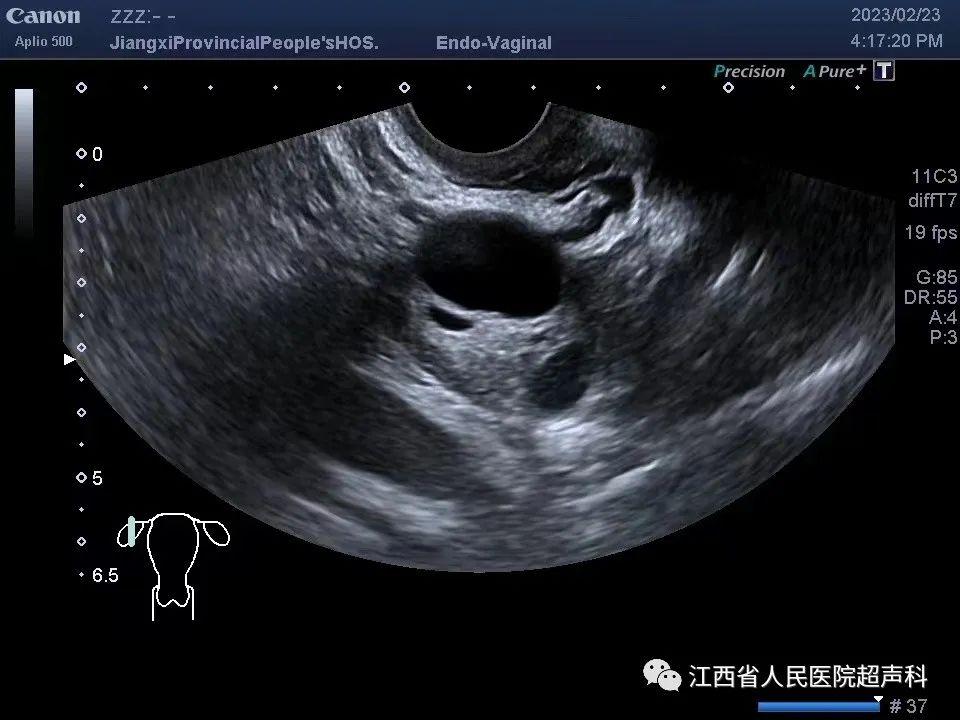

超声检查是卵巢囊肿最常用的检查方式,有*生活性**史者建议首选经阴道超声检查,无*生活性**或囊肿过大超出盆腔也可选择腹部超声检查。超声显示囊肿呈囊性无回声、囊壁薄、无实性成分、无分隔及血流信号者称为单纯囊肿。

超声显示囊肿内部有分隔伴异常回声称为单房性/多房性囊肿。

超声显示囊肿内含密集点状回声时,首先考虑为出血性囊肿(如黄体囊肿及子宫内膜异位囊肿等)。